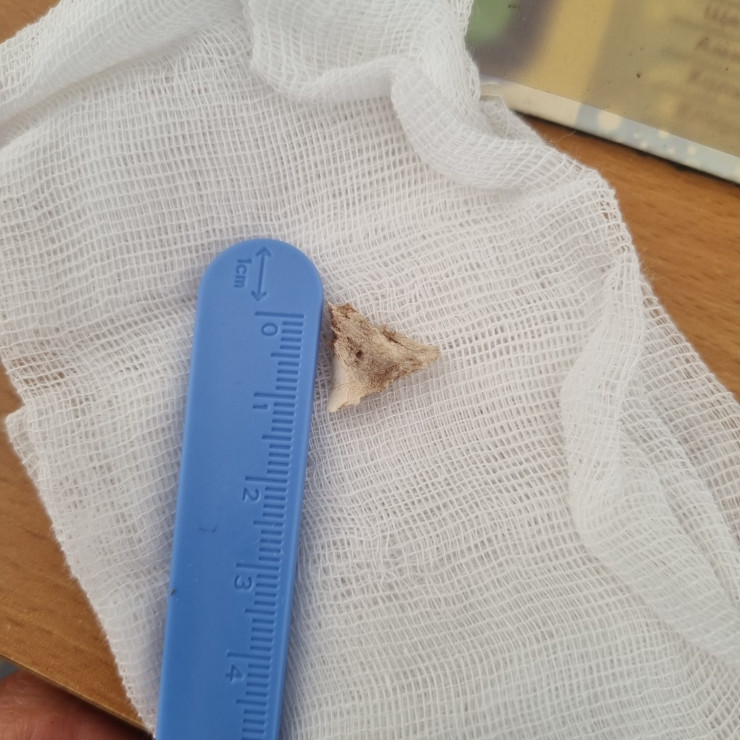

"Чтобы вытащить инородное тело, мы используем разные инструменты: щипцы, "корзинки" для захвата", - делится врач.

Перечень того, что вытаскивали из детских органов, огромный. Но чаще всего это монеты, камни, сережки, магниты и батарейки.

"Например, из кишечника 4-летнего малыша вытащили кольцо от связки ключей. Родители три недели не догадывались, что их ребенок проглотил его. Хотя он жаловался на боли в животе, рвоту. Потом обратились к нам. Под общим наркозом на ФГДС мы обнаружили инородное тело в 12-перстной кишке и извлекли его. Был еще случай недавно: мы вытащили из дыхательных путей 14-летнего подростка фонарик от зажигалки. Примечательно то, что юноша месяц ходил и никому не рассказывал об этом, пока при обследовании на рентгене случайно не обнаружили инородное тело в дыхательных путях", - рассказал Серик Нусипкожаев.